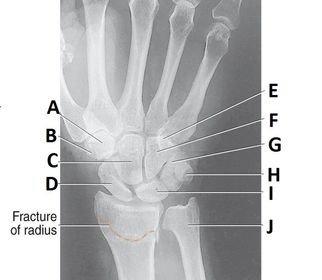

A. trapezoid B.. trapezium C. capitate D. scaphoid E. hamulus F. hamate G. triquetrium H. pisiform I. lunate J. ulna